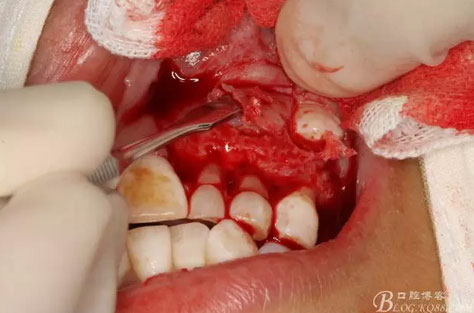

圖18.摘除囊腫后遺留的巨大骨腔

圖19.生理鹽水沖洗骨腔,修整骨腔表面

圖21.術中拍全景片,看是否有牙瘤殘留,發(fā)現左側乳Ⅱ根尖區(qū)還有少量致密鈣化物,建議拔除左側乳Ⅱ、,患者要求保留兩個乳牙。經協商,遺留極少量鈣化物,不影響整體愈合。通過骨腔探查,發(fā)現左側乳Ⅱ、Ⅲ根尖區(qū)未破壞,骨壁尚完整。同意遺留部分鈣化物。有點缺憾,為了保留乳牙和患者的美觀及功能。定期觀察遺留部分的發(fā)展變化

圖22.為了保留兩顆乳牙,不再去除遺留部分鈣化物,遂膠原蛋白海綿填塞兩個缺損骨腔。